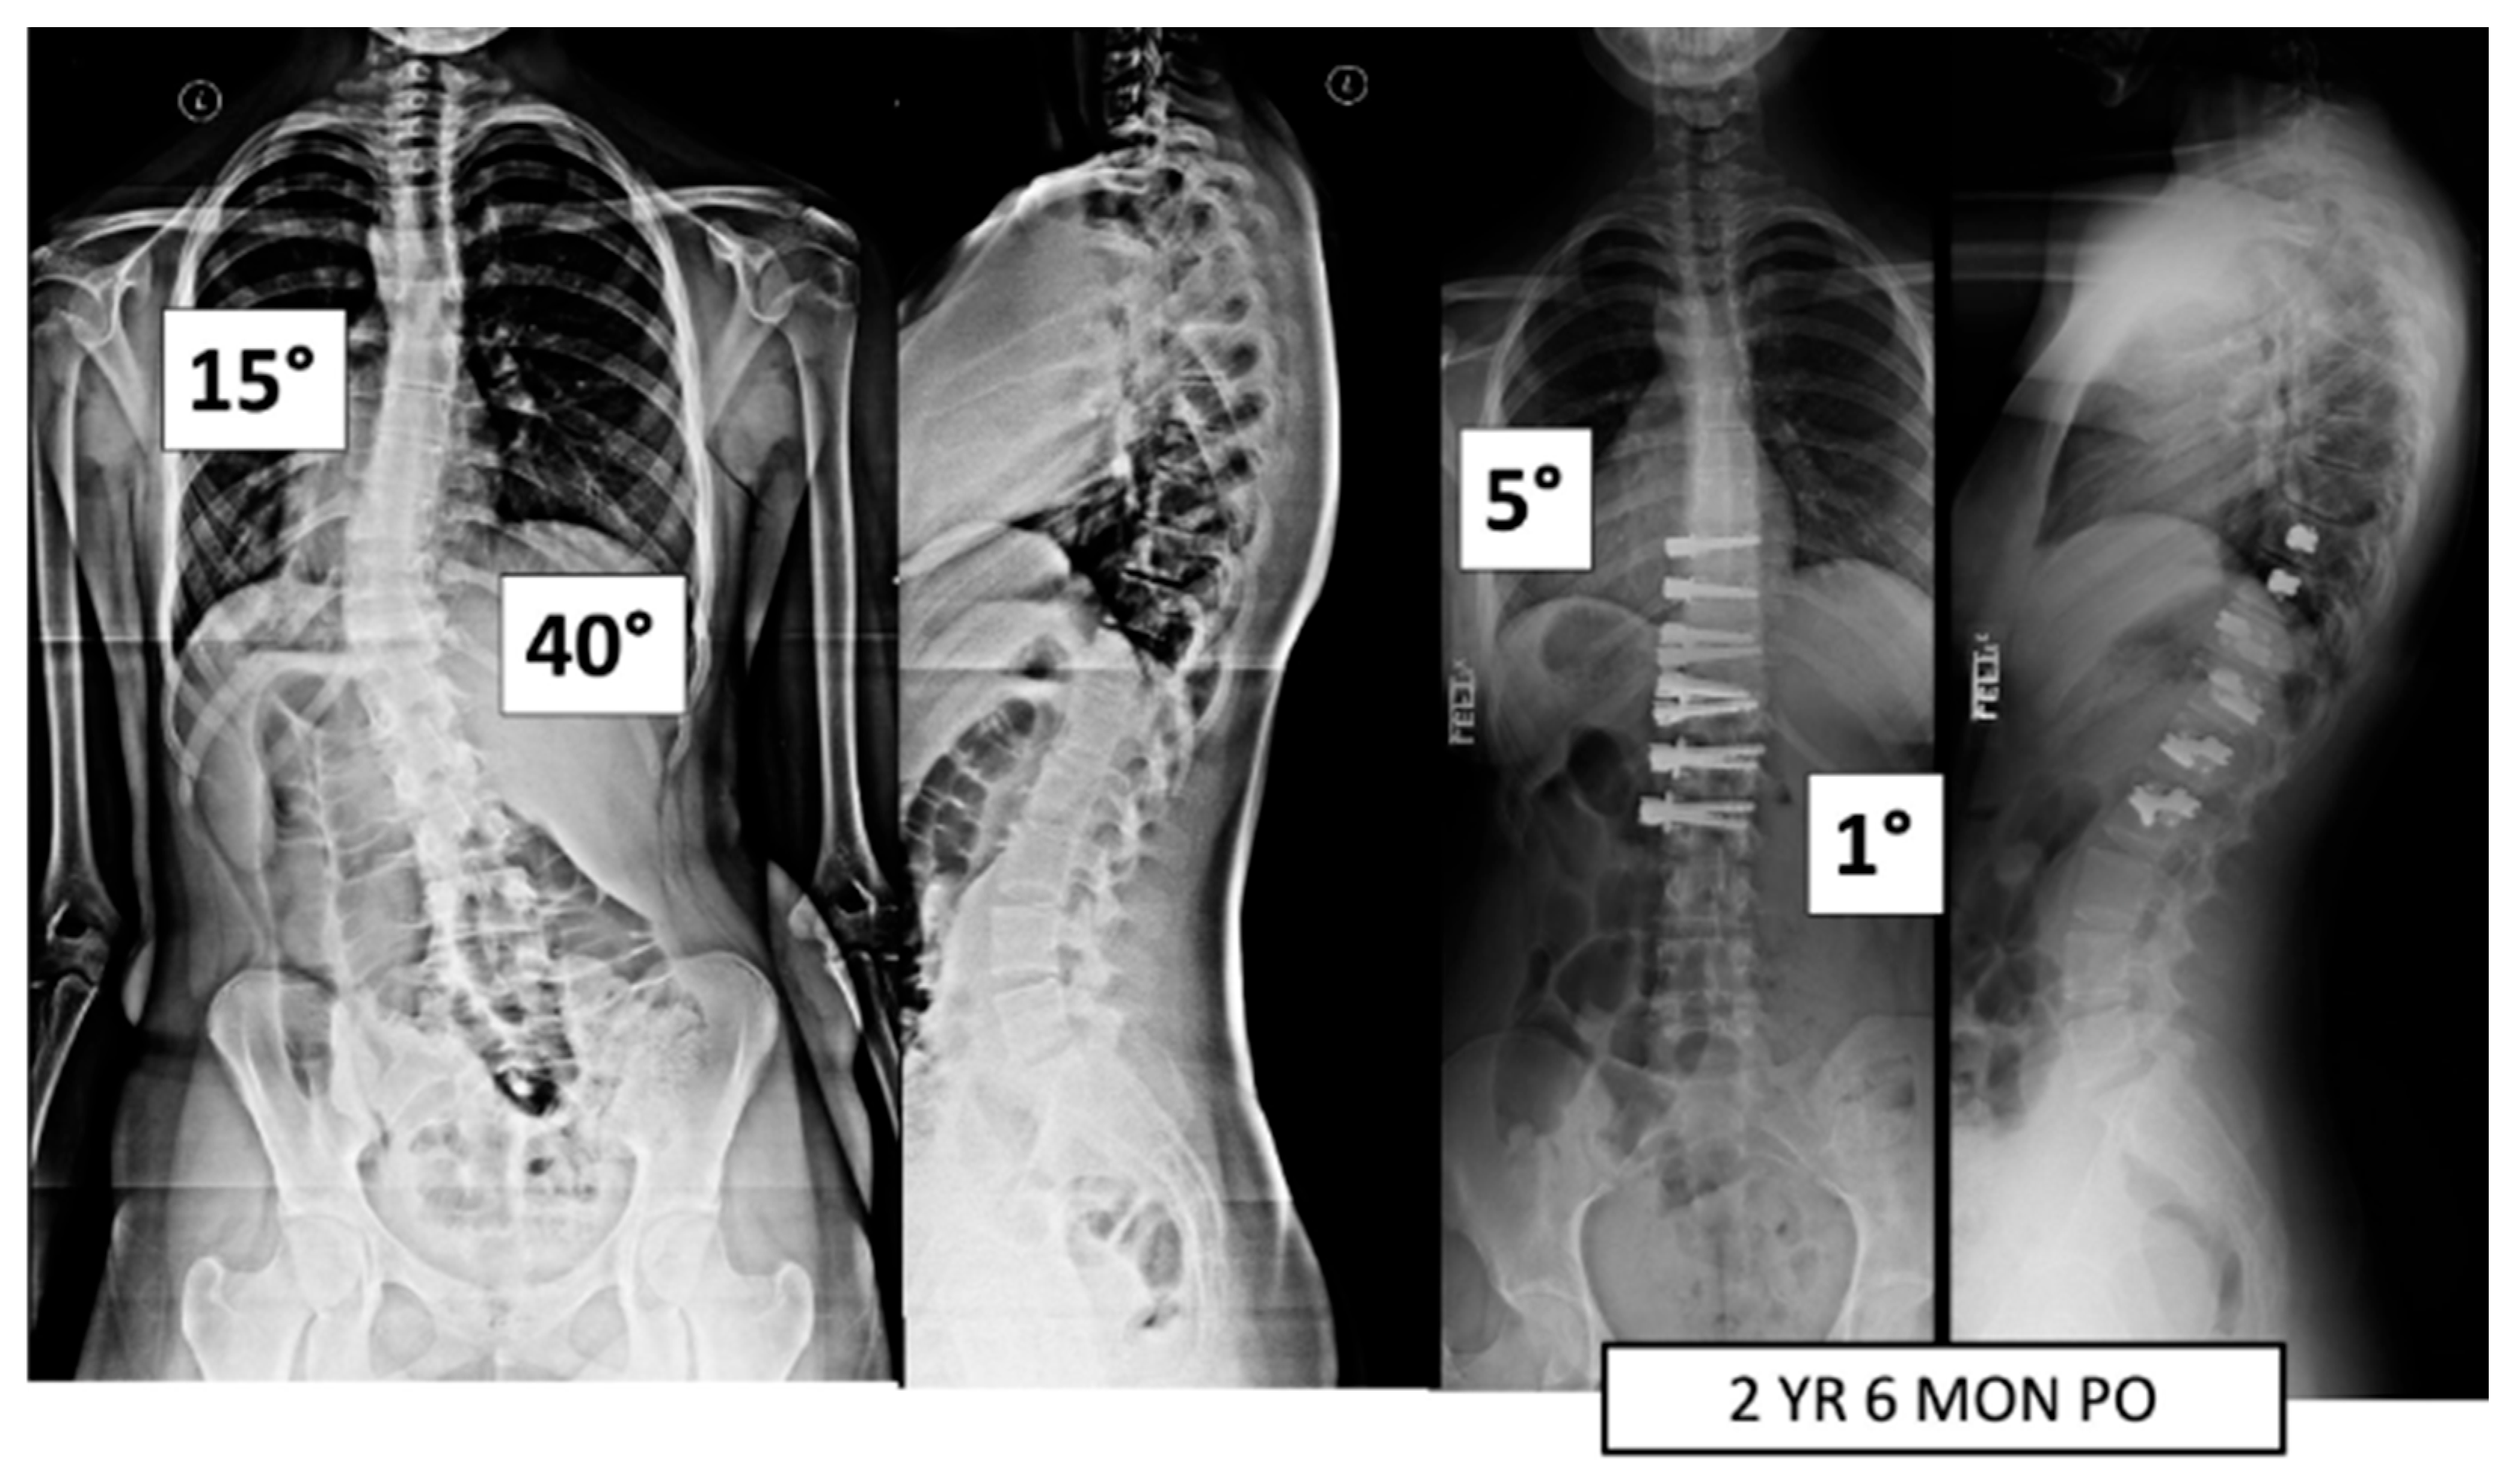

A total of 37 patients, age 14.1 ± 1.6 years, 86.5% female (Table 1), were included. Pre-operative major Cobb was 51 ± 8° and minor Cobb was 37 ± 13° (Figure 1 and Figure 2). Of the 27 Lenke 5 patients, 6 (22%) had their thoracic curve instrumented in addition to their thoracolumbar curvature. Of the 10 Lenke 6 patients, 9 (90%) had their thoracic curve instrumented as well. The mean FU was 35.9 ± 11.5 months.

Figure 2.

This is a 15-year-old female treated with lumbar VBT. At 2 years and 6 months post operation, she has resumed all activities with no complications.